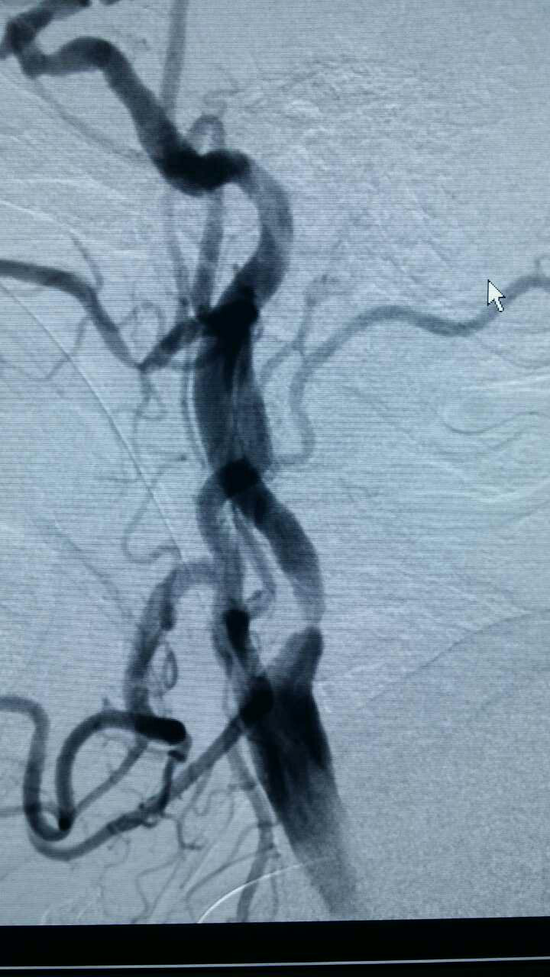

颈动脉血管造影图谱:[1]正常颈动脉血管造影

颈动脉狭窄绝非小事可致死可瘫痪医生总结了5条妙计助您预防![颈动脉血管造影图谱:[1]正常颈动脉血管造影](/image/loading.gif)